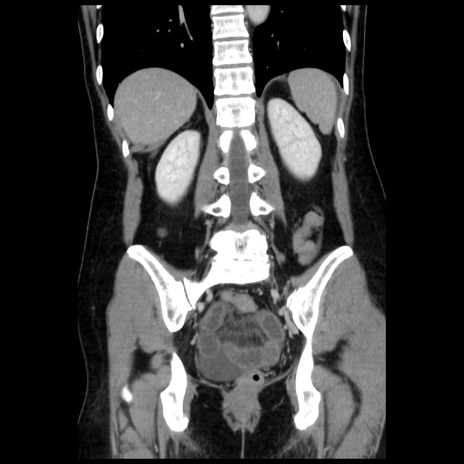

症例10(冠状断像)

【症例】 50歳代女性

【主訴】 腹痛

【現病歴】前日生レバーを食べた。今朝に排便あり。 昼前に突然発症の腹痛を生じ、当院救急外来を受診した。

【既往歴】 子宮筋腫にてで子宮全摘後

【身体所見】 意識清明、腹部:平坦、軟、下腹部やや左を中心に圧痛・反跳痛あり、筋性防御あり

【データ】WBC 7800、CRP 0.07